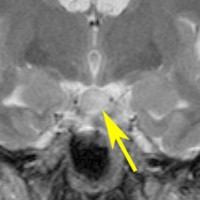

幼児期に思春期早発で発症

思春期早発で発症した幼児の視床下部過誤腫

視神経交叉の後方,乳頭体の前からぶら下がるようにしてあります

典型的な有茎状タイプです